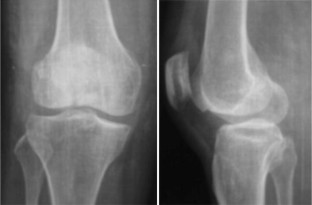

After an average follow-up period of 24 months (range 5–28 months), all fractures had healed. The average healing time was 11.6 weeks (range 9–14 weeks). On the version of the Knee Society Score modified by Dr. John Insall in 1993, the average score was 174.6 points (range 125–199 points).

Fig. 3

Fig. 4